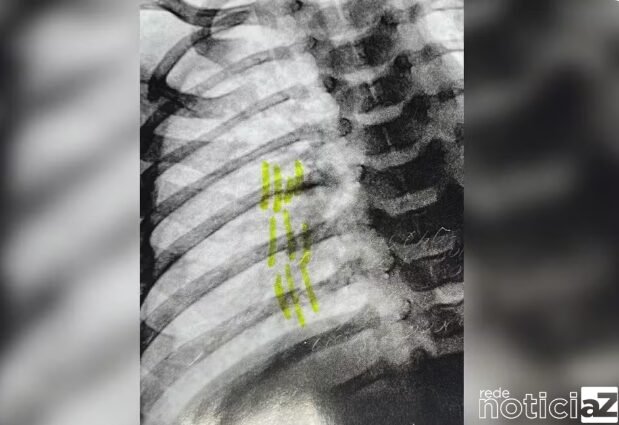

Um bebê com ferimentos graves recebeu alta da UTI da Unidade de Pronto Atendimento do Jacaré em Cabreúva nesta última terça-feira (15).

Sendo assim, o pai adotivo da criança foi preso e deve responder por lesão corporal, violência doméstica e maus-tratos.